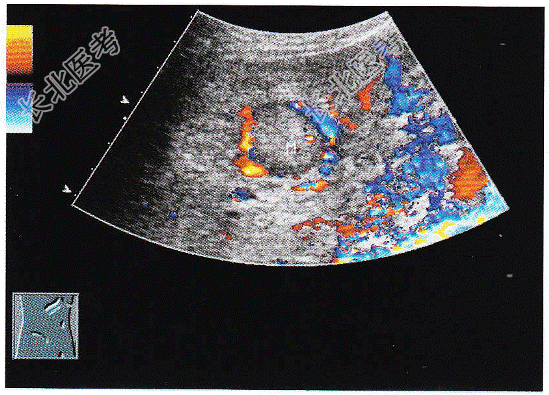

- 单项选择题临床资料:男性患者, 66岁;自述消瘦、腹胀不适; 患慢性乙型肝炎20年,

化验检查: AFP明显增高。

超声综合描述:肝表面不平, 肝回声不均,肝中裂增宽, 三支肝静脉变细,门静脉内径1.4cm, 左叶可见3.4cm×3.0cm中等回声区,周边有晕, CDFI:中等回声周边可见血管绕行。见下图及彩图。

超声提示: A、肝囊肿合并感染

B、肝腺瘤

C、肝硬化肝癌

D、肝血管瘤

E、肝脓肿